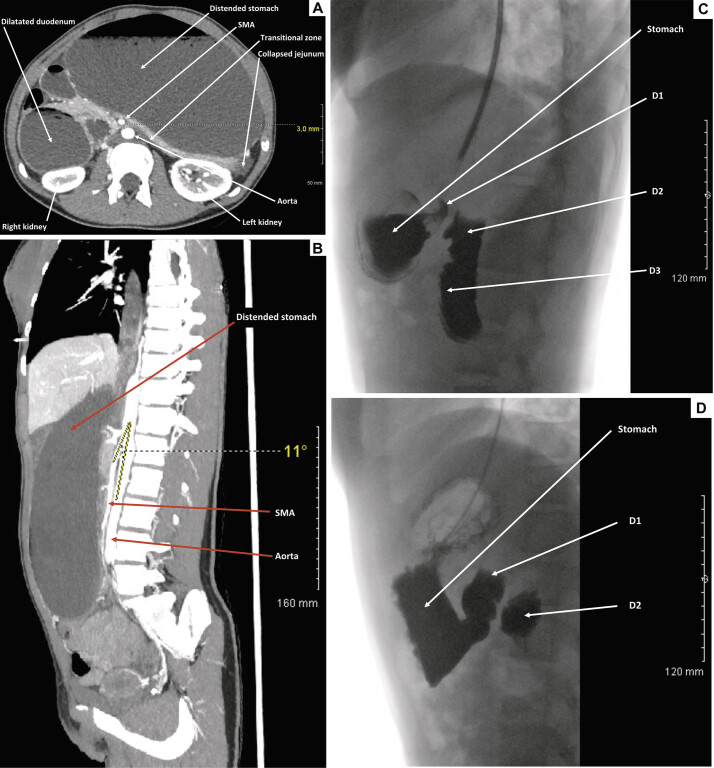

Superior mesenteric artery (SMA) syndrome is a rare cause of proximal bowel obstruction in pediatric surgery. We present the management of a rare, idiopathic, and acute form of SMA syndrome in a teenage girl, successfully treated with a robotic approach. A 14.5-year-old girl with no prior medical history and a normal body mass index (BMI) for her age (18.4 kg/m 2 ) was admitted to our department with acute proximal bowel obstruction syndrome. Initial imaging, including an abdominal X-ray, computed tomography scan, and upper gastrointestinal tract radiography, confirmed the diagnosis of SMA syndrome. Conservative management was initiated with nasogastric tube placement, postural adjustments, and optimal nutritional support. However, symptoms persisted, and surgery was performed 5 months after the initiation of conservative treatment. A robotic-assisted duodenojejunostomy, preserving the fourth portion of the duodenum, was performed without intraoperative complications. Postoperatively, the patient experienced immediate symptom relief and was discharged on postoperative day 4. The postoperative course and long-term follow-up (7 years) were uneventful. This case report describes an acute, idiopathic form of SMA syndrome successfully treated with robotic-assisted duodenojejunostomy in a teenage girl with a normal BMI. To our knowledge, this is only the second reported case of robotic surgery for SMA syndrome in the pediatric literature.